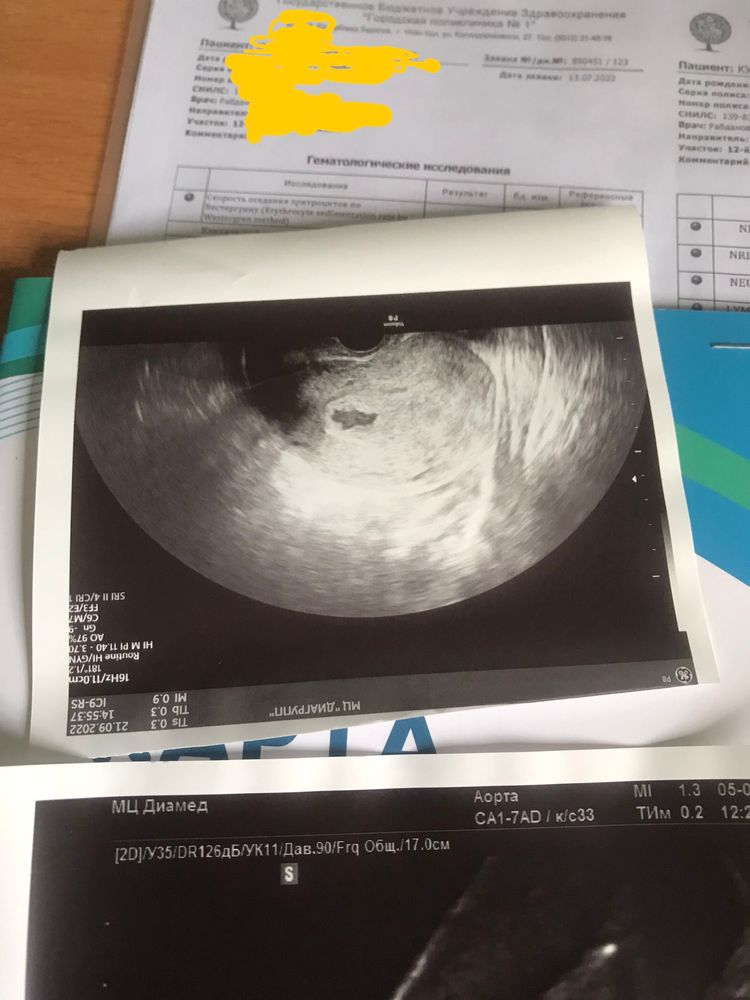

Врач посмотрела оба результата анализа ХГЧ, спросила о том, что может быть что-нибудь кровит или болит. Но ни чего подобного не было. Тогда она посмотрела меня на кресле (все осмотры там делают при помощи трансвагинального УЗИ). Полость плодного яйца в матке есть, но оно не круглое или овальное, а с волнистыми краями.

Сказала что возможно это анэмбриония или ЗБ. Но возможно, есть вариант того что последний результат ХГЧ был ошибочным, что это простая лабораторная ошибка, потому как плодное яйцо есть, хотя оно странноватое. Поэтому она говорит, что бы я продолжила прием Утрожестана и снова пересдать анализ через 2-3 дня.

Обо всем этом (вместе с фоткой плодного яйца), я отправляю сообщением С.Ю. И спрашиваю о том, есть ли шанс. Но она огорчает, т.к. ХГЧ падает и скорее всего шансы близки к нулю.